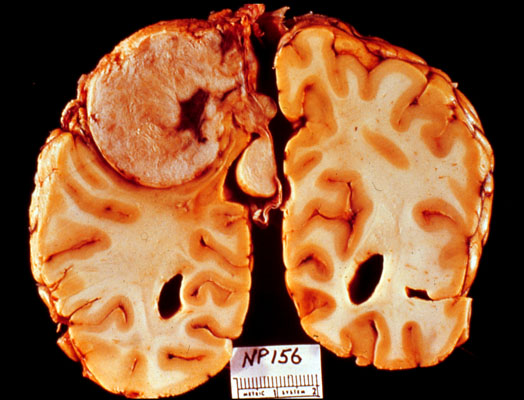

Meningioma

The tumor is well circumscribed and sharply demarcated from the compressed cerebral hemisphere.